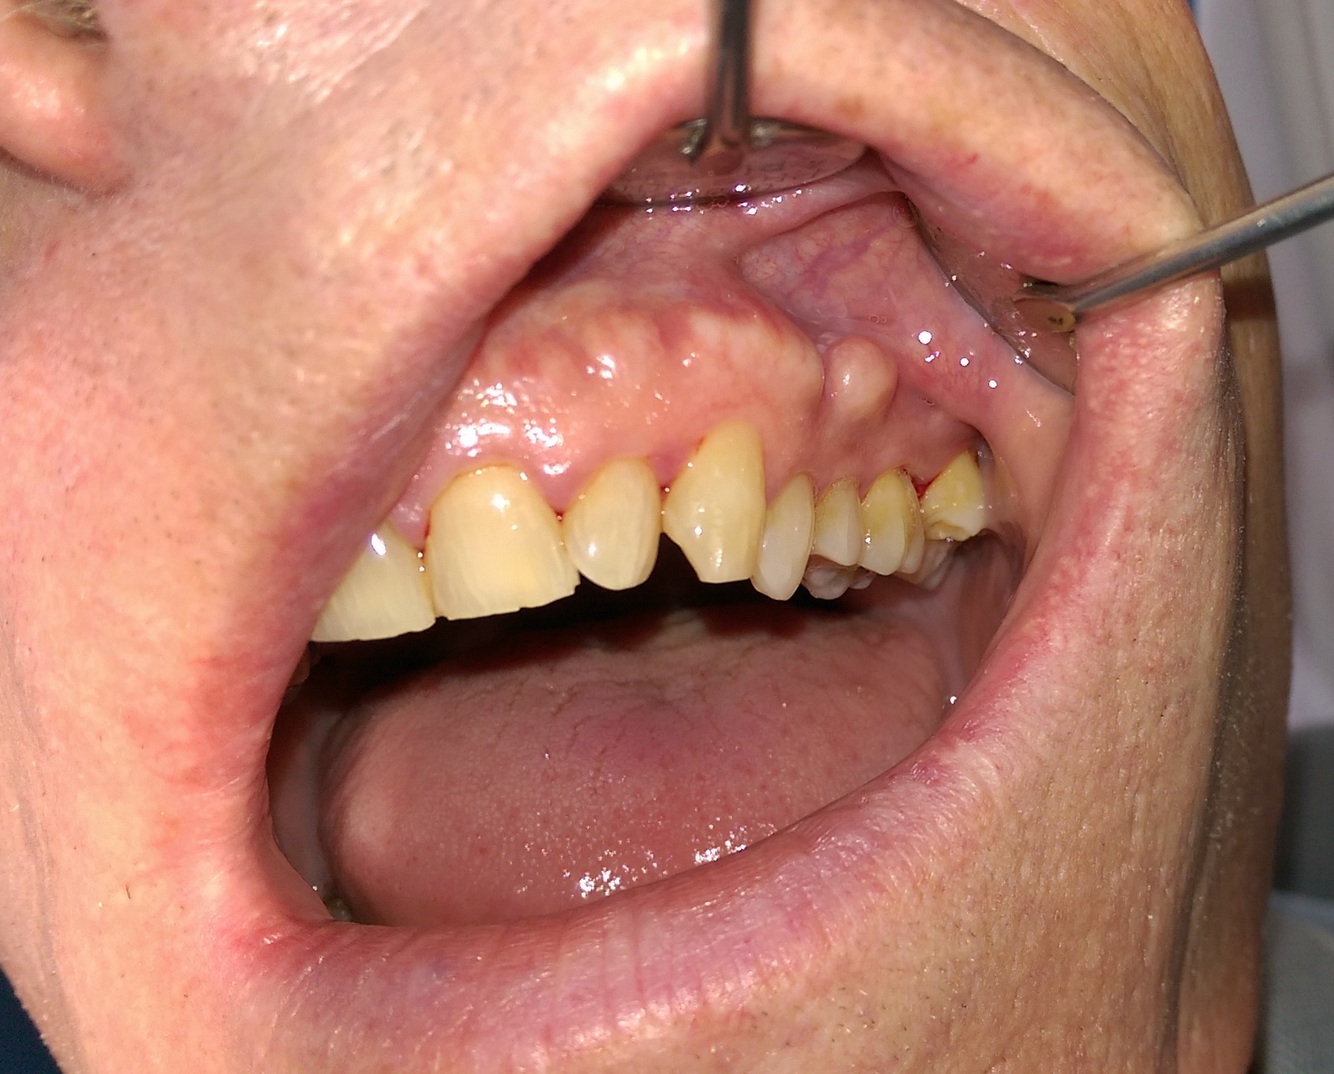

Fordyce Granules what is it

Fordyce Granules Location

Fordyce Granules Appearence

Clusters of tiny yellow lobules.

Fordyce Granules Demographic

Over 80% of adult